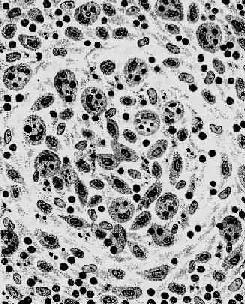

伤寒杆菌引起的炎症属急性增生性炎症,主要是巨噬细胞的增生。其吞噬能力十分活跃,胞浆中常吞噬有伤寒杆菌、受损的淋巴细胞、红细胞及坏死细胞碎屑,在病理诊断上具有一定的意义,故常称这种细胞为伤寒细胞。伤寒细胞常聚集成团,形成小结节,称为伤寒肉芽肿或伤寒小结(图18-19)。革兰染色可见伤寒细胞胞浆内含有被吞噬的伤寒杆菌。伤寒杆菌引起的炎性反应的特点是病灶内无中性粒细胞渗出。

图18-19 伤寒肉芽肿模式图

图示伤寒小结内大量增生的伤寒细胞,胞浆内含有红细胞及组织碎屑等